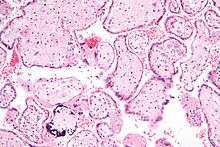

Micrograph of CMV placentitis.

Micrograph of CMV placentitis. A 3D Power doppler image of vasculature in 20-week placenta